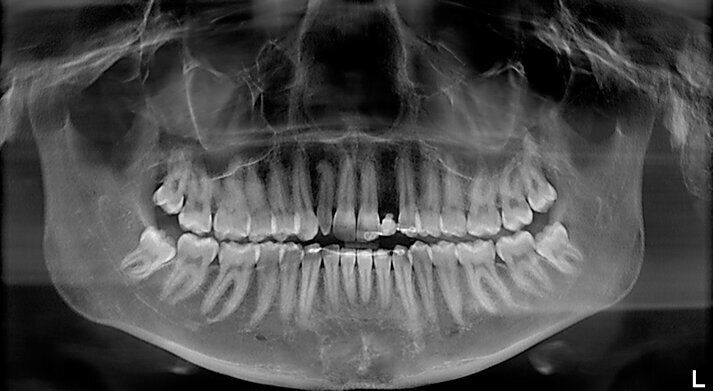

Fig. 1 - OPT delle arcate dentarie, si noti anomalia di forma elemento 12 e sito edentulo in sede 22.

Fig. 4a - Rx endorale pre-operatoria sito edentulo sede 22. Misurazione dello spazio inter-radicolare per l’inserimento dell’impianto.